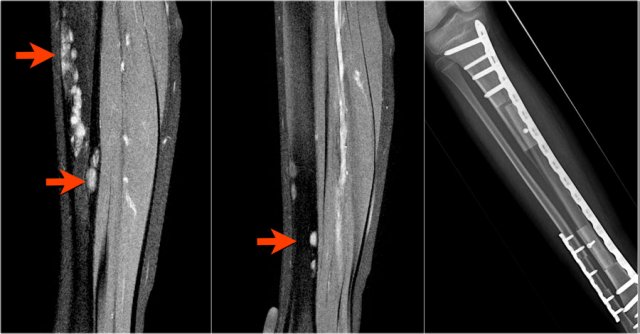

Adamantinoma (4)

On the left a radiograph and CT-image of another typical adamantinoma.

CT was performed prior to biopsy.

Here a mixed sclerotic-lytic lesion, cortically based in the tibia shaft in a 12-year old boy.

There is also a lucent lesion in the cortex of the fibula.

Differential diagnosis includes adamantinoma or osteofibrous dysplasia, based on the typical location, age (2nd-3rd decade) and radiographic appearance.

Biopsy showed adamantinoma.

Continue with the MR.

Same patient.

Sagittal T2-weighted fat-suppressed images demonstrate multiple foci of high SI within the cortices of tibia and fibula.

Post-operative situation on the right.

Care should be taken that each focus is entirely removed.

MRI is pivotal for demonstrating the intramedullary and soft tissue extension.